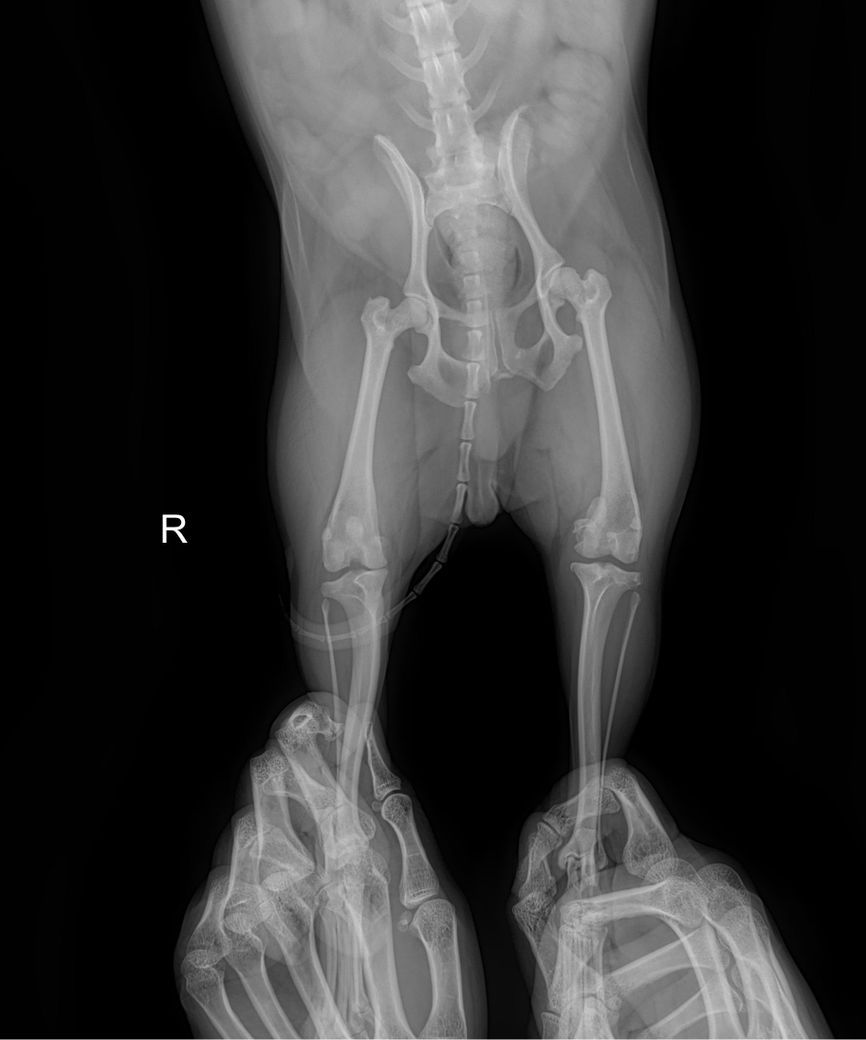

강아지 슬개골 탈구 엑스레이 봐주세요

제 반려견이 다리 한쪽이 아파보여서 병원 데려갔는데 뒷다리가 슬개골 탈구 심하다고 3기에서 4기로 넘어가고 있다고 하더라구요 이제 슬슬 수술 할려고 하는데 철심을 박아야 한다고 하더라구요 선생님들이 봐주셨을 때 정말 심해보이나요?ㅠㅠㅠㅠㅠ 왼쪽 , 오른쪽 중 어디인가요 너무 놀라서 헷갈려요 ㅠㅠ

좌측 슬개골이 내측으로 탈구되어 있는 상태이며.

외측상에서 슬관절 관절낭의 종창이 뚜렷하게 관찰되어 슬개골 탈구와 함께 십자인대의 부분적 손상 가능성이 강력히 의심됩니다. 주치의의 지시대로 빠르게 수술 진행하는게 도움이 됩니다.